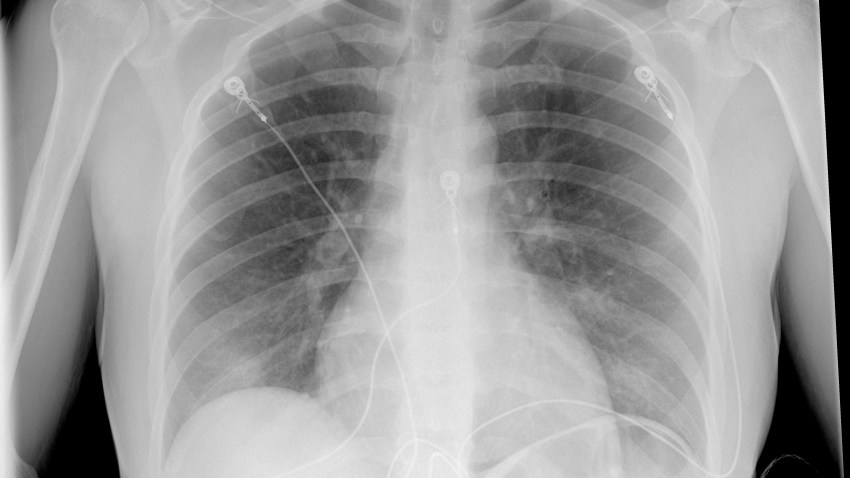

Rayos X Pulmones Covid 19

Radiografias De Torax Para Detectar La Covid 19

Foto Premium Imagen De Rayos X Del Torax Humano Para Un Diagnostico Medico Coronavirus Covid 19 Sindrome Respiratorio Del Virus De La Epidemia 2019 Ncov

Imagenes De Rayos X Pueden Ser Inadecuadas Para Diagnosticar La Covid 19 Radiografia Medimaging Es

Coronavirus Como Ataca El Covid 19 Los Pulmones Y Que Danos Causa Estas Radiografias Lo Revelan Marca Claro Mexico

Coronavirus Los Rayos X Muestran La Forma En Que La Infeccion Por Covid 19 Destruye Los Pulmones Observatorio Regional De Tuberculosis De Las Americas

La Impactante Imagen Del Efecto Del Coronavirus En Los Pulmones Ser Lanzarote Cadena Ser

Los Radiologos Muestran Imagenes De Lo Que Hace El Coronavirus En Los Pulmones

Las Radiografias De Torax Ayudan A Predecir La Gravedad Del Covid 19

Imagenes De Rayos X De Los Pulmones Para Diagnosticar La Covid 19 Portal Universidad De Sevilla

Hallazgos Radiologicos De 81 Pacientes Con Neumonia Por Covid 19 En Wuhan Covid 19 Intramed

idescubre.fundaciondescubre.es